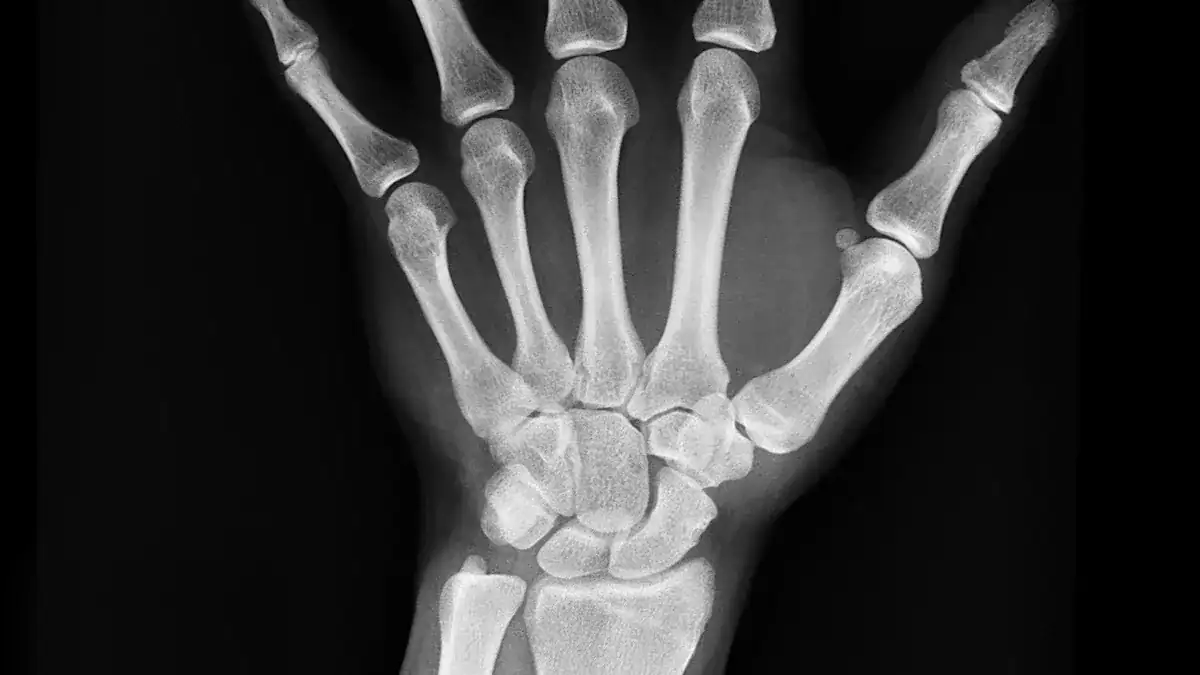

To get a clearer picture, your doctor may order imaging tests. These tests help them see the bones and soft tissues in your wrist. Common tests include:

X-rays: These show bone fractures or arthritis. Sometimes, you need repeat X-rays after 10-14 days.

CT scans: These provide more detailed images of bones.

MRIs: These show soft tissues like ligaments, tendons, and cartilage.

Ultrasounds: These can visualize soft tissues and nerve compression.